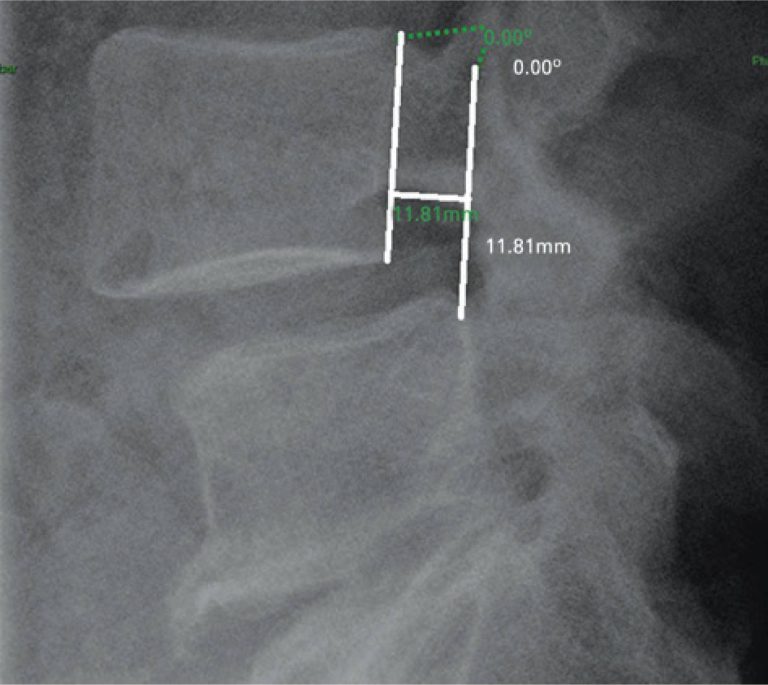

Interobserver reproducibility of radiographic evaluation of lumbar spine instability

DOI: 10.1590/S1679-45082016AO3489

ABSTRACT Objective: To measure the interobserver reproducibility of the radiographic evaluation of lumbar spine instability. Methods: Measurements of the dynamic radiographs of the lumbar spine in lateral view were performed, evaluating the anterior translation and the angulation among the vertebral bodies. The tests were evaluated at workstations of the organization, through the Carestream Health Vue RIS (PACS), version 11.0.12.14 Inc. 2009© system. Results: Agreement in detecting cases of radiographic instability among the observers varied from 88.1 to 94.4%, and the […]